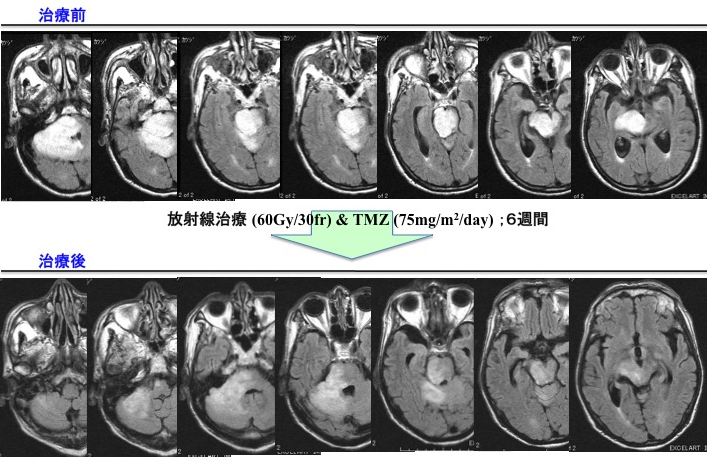

Grade 4(膠芽腫):手術+放射線治療+化学療法(TMZ±Bev(アバスチン))±交流電場腫瘍治療(NovoTTF)

放射線治療に化学療法を併用します。(治療期間は6週間ですが、高齢者の場合は放射線治療を3週間に短縮して行うこともあります。その場合でもTMZは6週間使用します。)